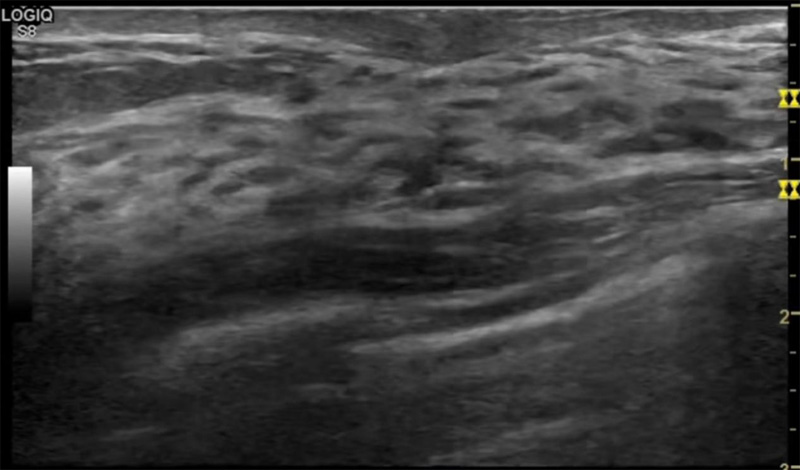

乳腺病變最常用的檢查方法乳腺超聲設(shè)備發(fā)揮作用

乳腺超聲設(shè)備便捷安全的檢查方法,國(guó)際上有乳腺檢查超聲的指南??梢葬槍?duì)乳腺疾病做出系統(tǒng)的分類?!度橄俪暼舾膳R床常見問題專家共識(shí)(2018版)》說明不建議提示乳腺增生癥。單純的囊腫,乳腺改變等。在BI-RADS分類中已經(jīng)納入不同類別。針對(duì)未發(fā)現(xiàn)占位的乳腺,雙乳未見占位性病變(BI-RADS 1類)。因此看到這樣的檢查報(bào)告時(shí)候,不用緊張擔(dān)心,占位性結(jié)節(jié)沒有形成。